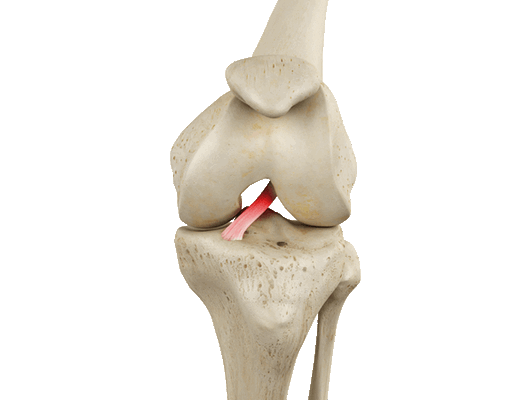

Передняя крестообразная связка отвечает за динамическую устойчивость коленного сустава, фиксируя голень от нефизиологического смещения кпереди и поддерживая наружный мыщелок большой берцовой кости. Более 1/2 стабильности коленного отдела обеспечивается благодаря ПКС. Именно поэтому данную структуру специалисты называют первым стабилизатором колена, без нее сустав нормально работать не сможет. Располагается она в самом центре костного соединения, перекрещиваясь с задней крестообразной связкой х-образно, что и дало этим двум структурным элементам одноименные названия. Мы же будем говорить сейчас конкретно о ПКС и посттравматической реконструктивно-пластической ее коррекции.

Из-за деструктуризации фронтальной крестовидной связки страдает биомеханика сочленения в целом: возникает нестабильность сустава и патологическое смещение суставных поверхностей относительно друг друга. Это неблагоприятным образом воздействует на хрящевые покрытия взаимодействующих костных единиц - они начинают страдать от нерациональных нагрузок при движениях. Если вовремя не откорректировать связочный аппарат, может развиться гонартроз, который приводит к серьезным дегенерациям не только суставного хряща, но и менисков.